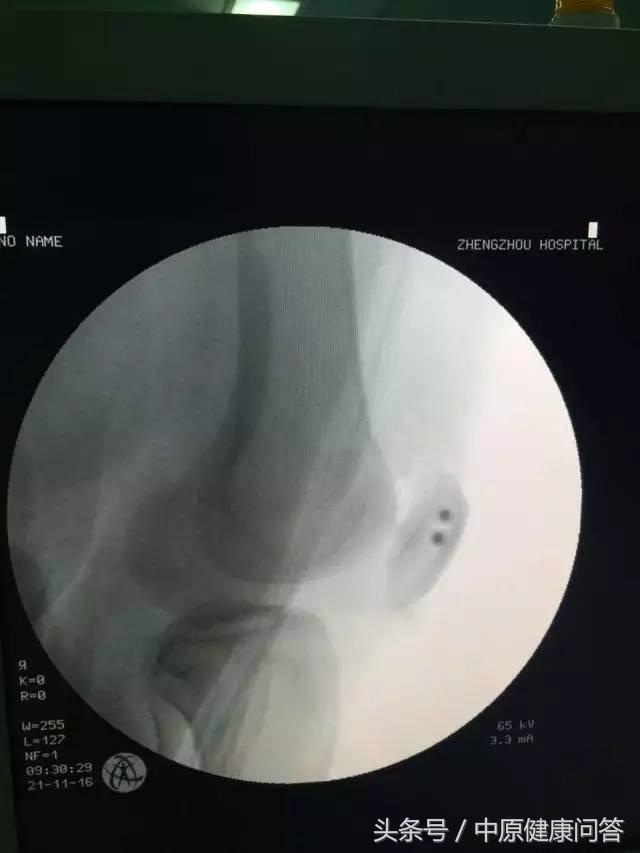

CT 检查

手术中

术后复查